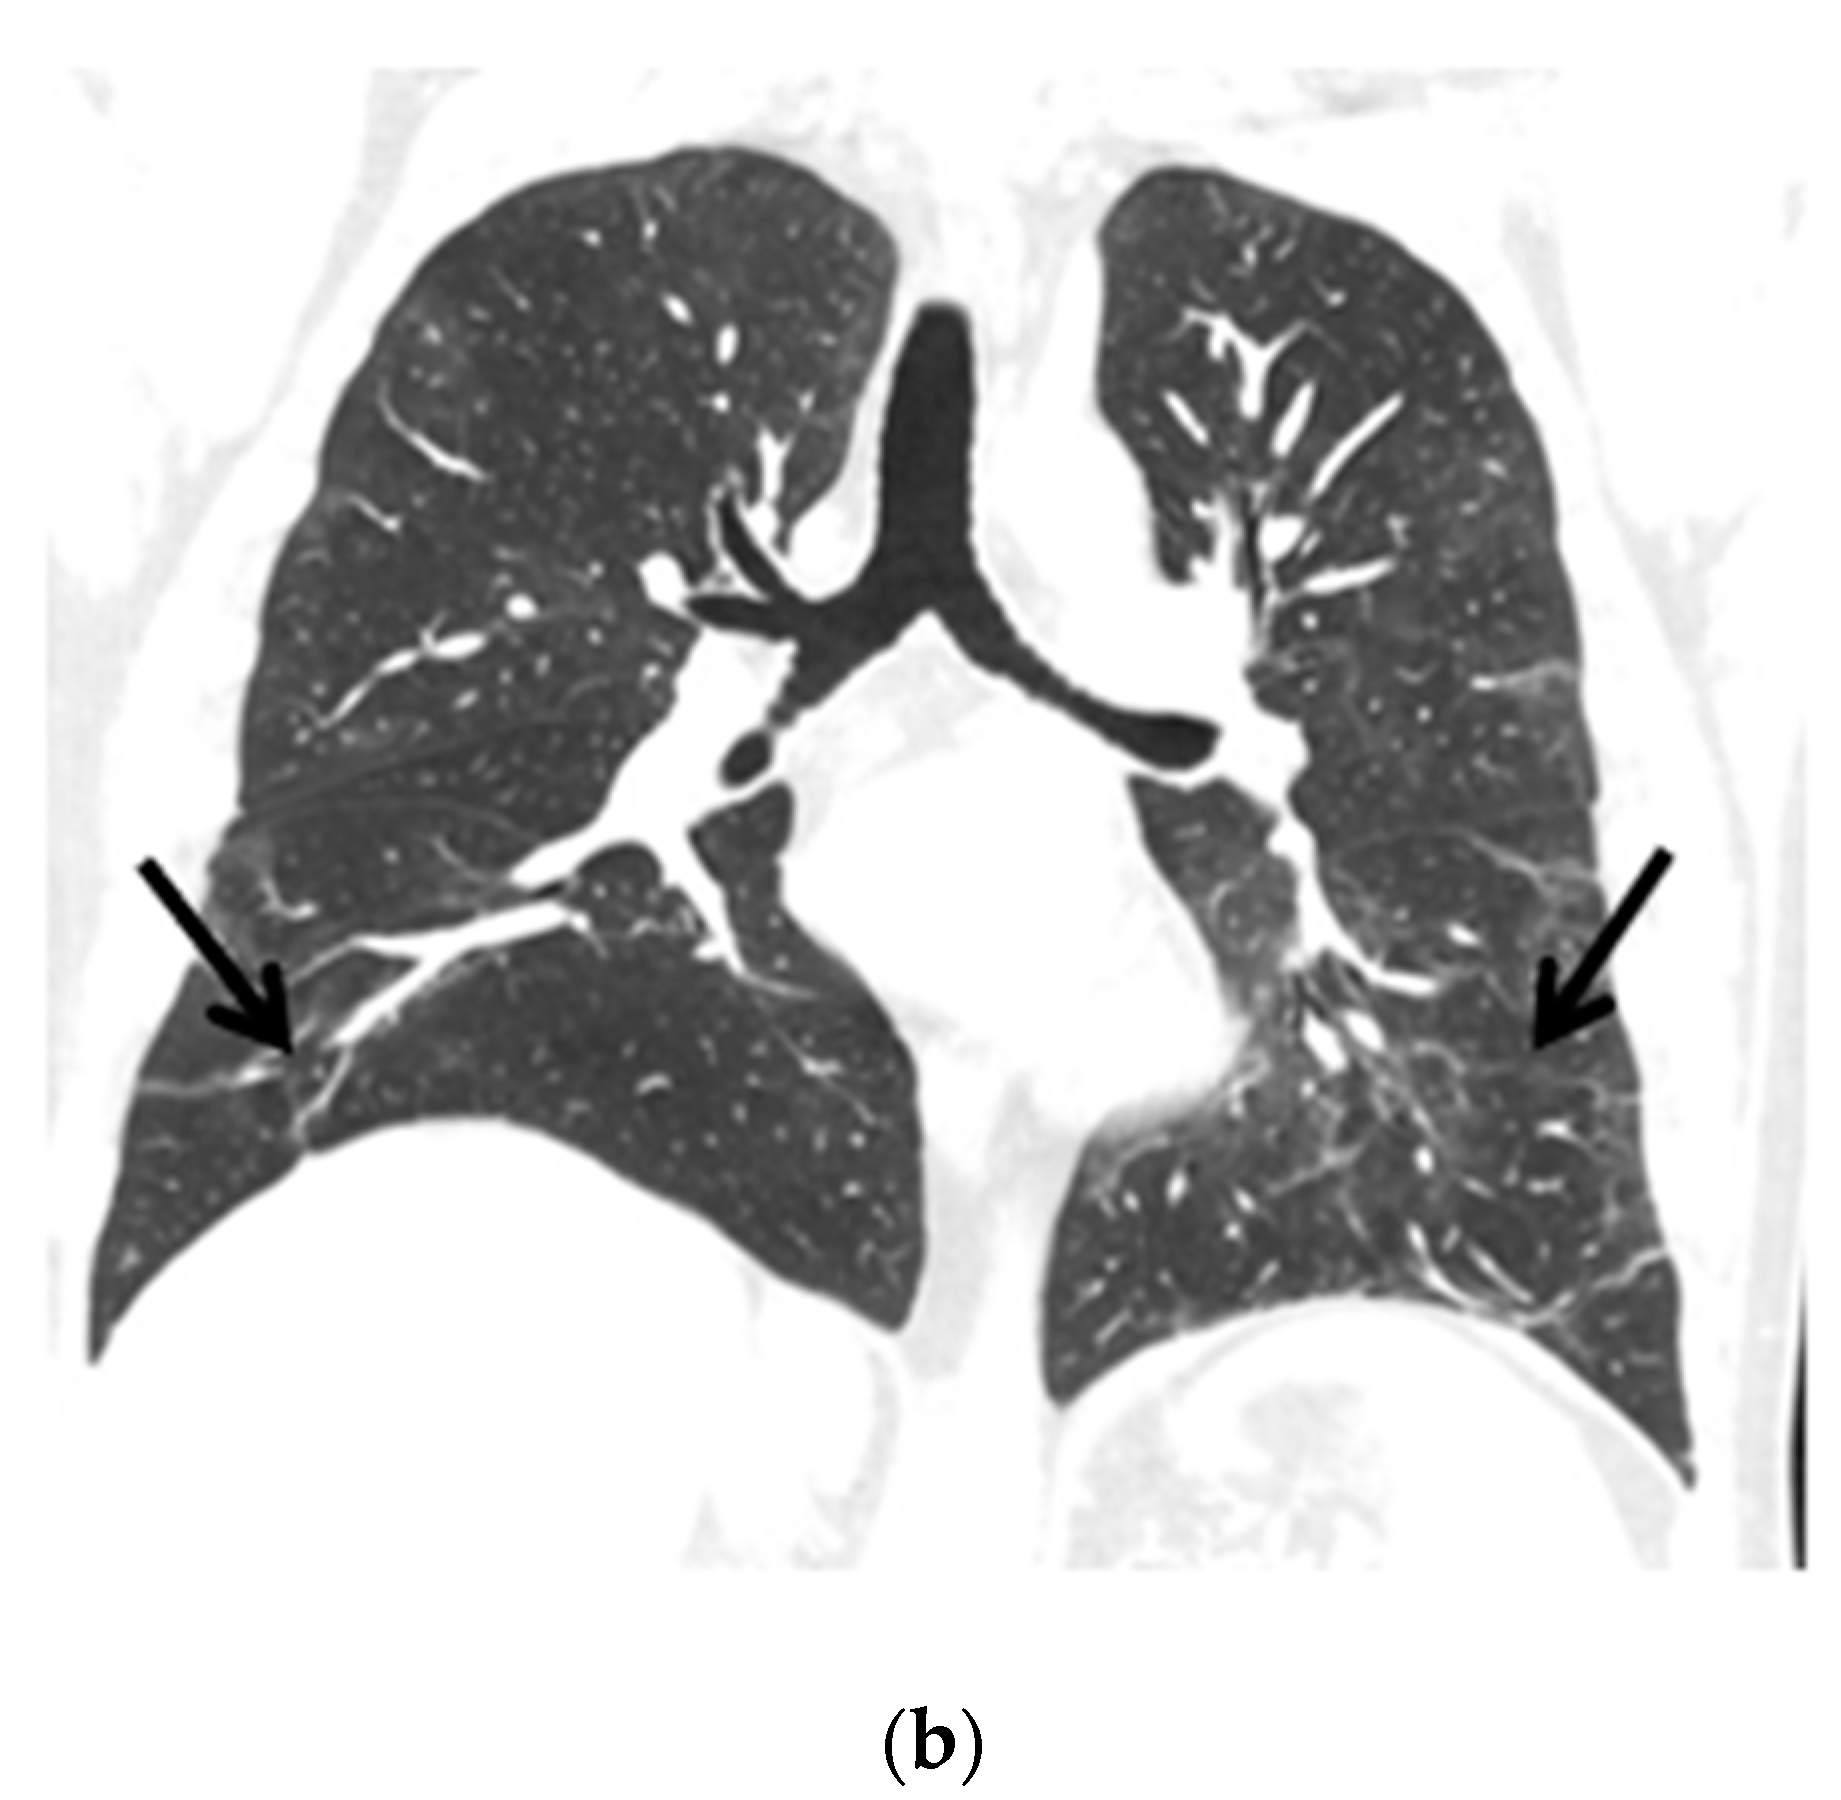

The control chest X-ray showed an almost complete regression of parenchymal lung disease, compared to the initial examination (Figure 1b). A follow-up CTPA showed complete regression of pulmonary embolism (Figure 2a,b); moreover, significant regression of parenchymal lung disease was found (Figure 3a,b).

Figure 3.

(a) Chest CT scans (lung window, coronal view) show patchy ground-glass opacities in accordance with COVID-19 dominant in the peripheral zones of the lower lungs (black arrows); (b) Chest CT scans (lung window, coronal view) after six months of follow-up show resolution of lung lesions (black arrows).